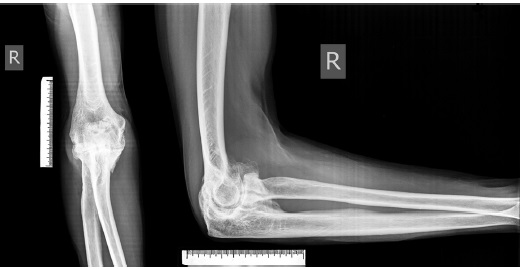

Первый этап. Для уточнения этиологии контрактуры пораженного сустава и исключения костных нарушений интактного локтевого сустава у пациента выполняют рентгенографию обоих локтевых суставов в двух проекциях (рис. 1).

Рис. 1. Рентгенограммы пораженного локтевого сустава в прямой и боковой проекциях: отчетливо видны признаки деформирующего артроза — сужение суставной щели, массивные оссификаты

Fig. 1. X-rays of the affected elbow joint in the anteroposterior and lateral views: signs of deforming osteoarthritis — narrowing of the joint gap, massive ossificates